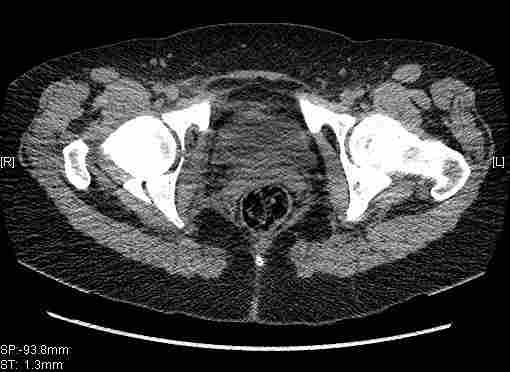

Удалось сегодня вывести пациентку в соседнюю больницу, где есть кт. Срезы сделаны только горизонтальные.

|

Уважаемый Коваленко А.Н., снимки плохого качества и нет уверенности, что задняя колонна сломана (смещена). Если кт нет - везите больную в рентгенкабинет (палатником качественные снимки снимки не получатся) и сделайте обзорный снимок таза, Judet и может быть inlet, хуже вы ей не сделаете.

От этих данных и будет зависеть тактика и прогноз.